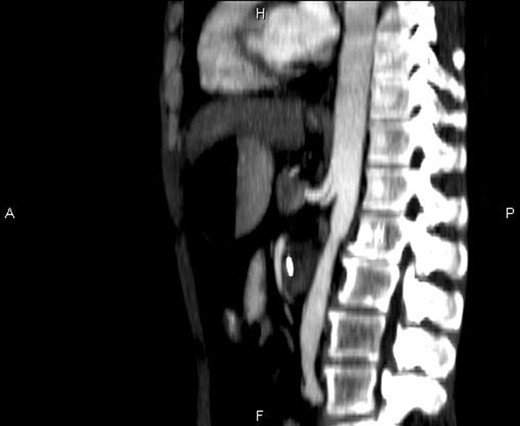

Computerized tomography (CT) scan of the upper and lower abdomen excluded the possibility of a tumor or an annular pancreas to be the cause of the compression of the duodenum. The subsequent CT scan showed an acute angle of 15° (Figs. 2 and 3) between the superior mesenteric artery and the aorta.

Sagittal CT image showing the entrapment of the duodenum between the aorta and the SMA.